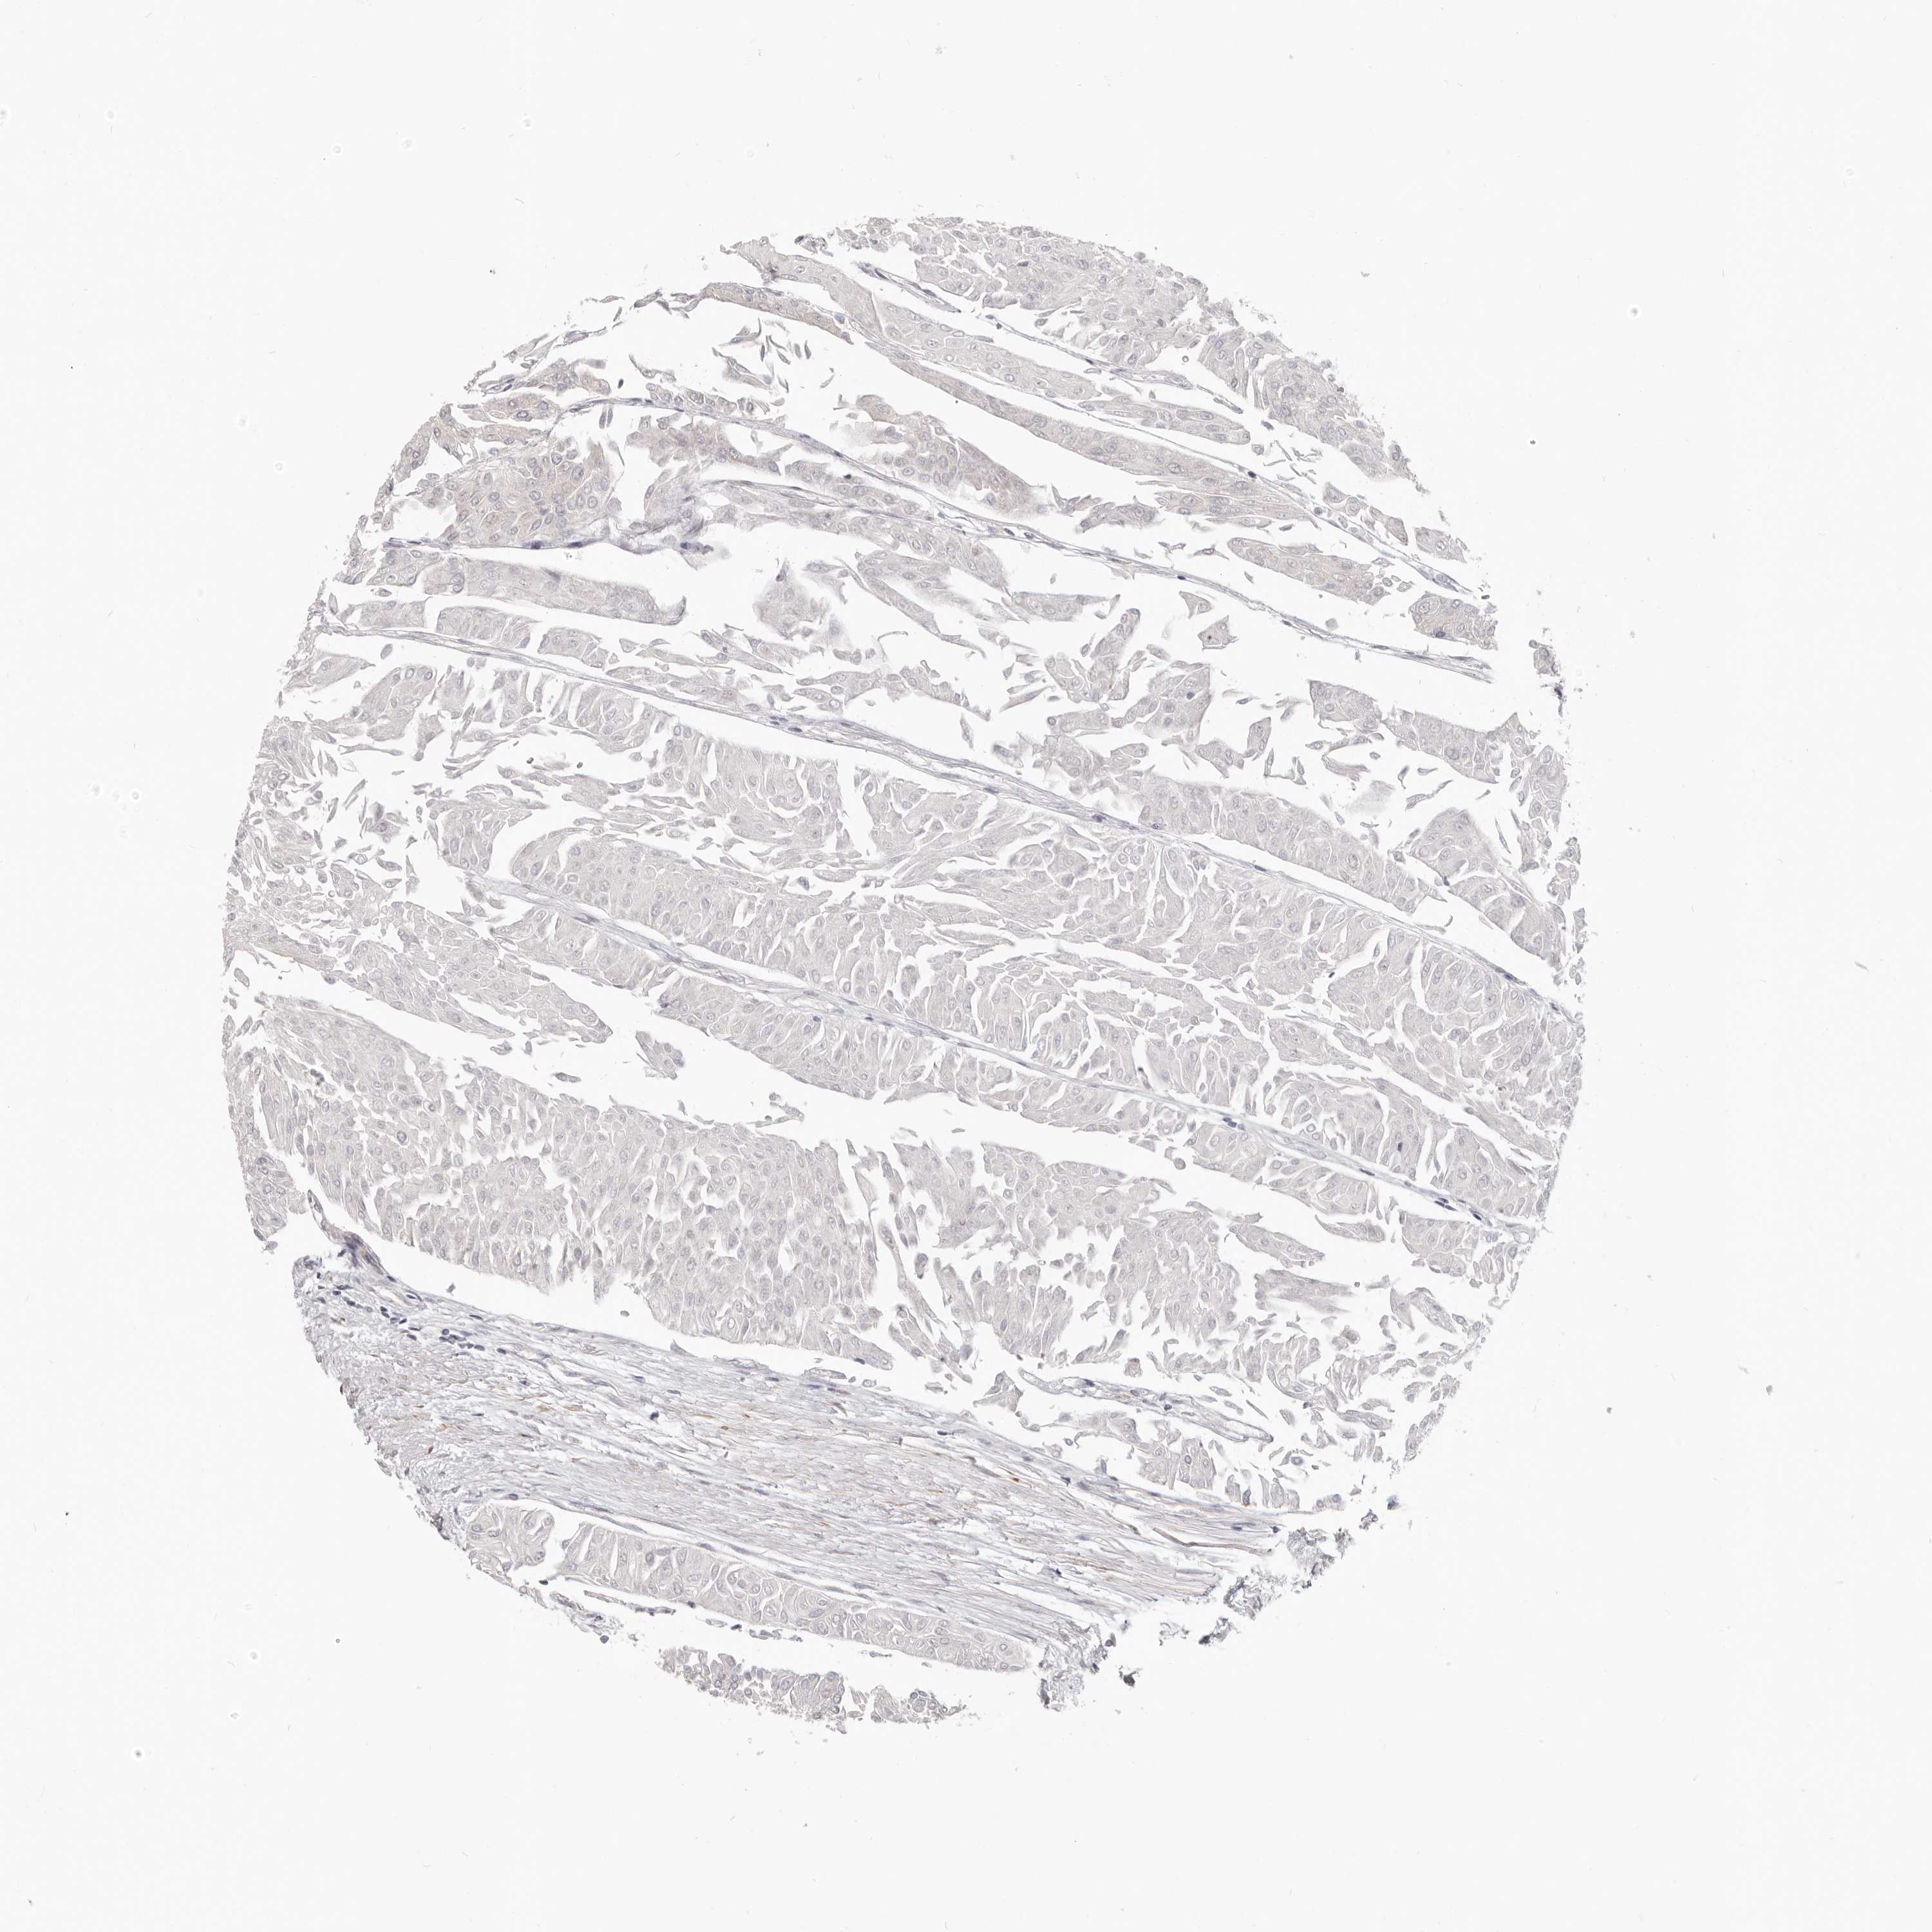

UROTHELIAL CANCER - Protein expressioni

A mouse-over function shows sample information and annotation data. Click on an image to view it in a full screen mode. Samples can be filtered based on level of antibody staining by selecting one or several of the following categories: high, medium, low and not detected. The assay and annotation is described here.

Note that samples used for immunohistochemistry by the Human Protein Atlas do not correspond to samples in the TCGA dataset.

Antibody stainingi

Antibody staining in the annotated cell types in the current human tissue is reported as not detected, low, medium, or high, based on conventional immunohistochemistry profiling in selected tissues. This score is based on the combination of the staining intensity and fraction of stained cells.

Each image is clickable and will lead to virtual microscopy that enables deeper exploration of all samples and also displays staining intensity scores, fraction scores and subcellular localization as well as patient and tissue information for each sample.

Antibody HPA029272

Staining

High

Medium

Low

Not detected

Intensity

Strong

Moderate

Weak

Negative

Quantity

>75%

75%-25%

<25%

None

Location

Urothelial carcinoma, Low grade

Urothelial carcinoma, High grade